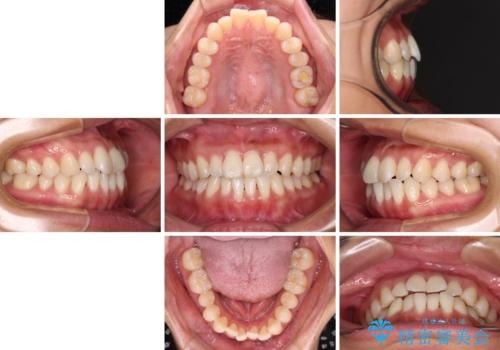

- 前歯のデコボコで前方に出ていることを気にして来院された患者様です。

上顎前歯が捻れて前方に飛び出しており、下顎前歯もそれに沿うようにデコボコとなっていました。

IPR(歯と歯の間を削る処置)によりスペースを獲得して上下顎前歯のデコボコを改善し、飛び出している前歯が引っ込むように設定し、インビザラインにて矯正治療を行うこととしました。

装着時間を守ってくださったので、予定通りの期間で終えることができました。インビザライン特有の、奥歯の咬み合わせの問題もなく、しっかりと歯列を改善することができました。